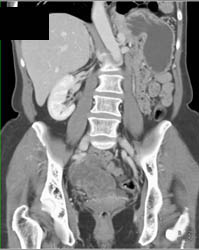

Diagnosis

Gastric Cancer